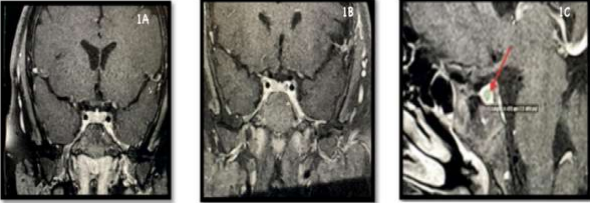

A 1.5 Tesla nuclear magnetic resonance of the sellar region revealed a normal signal and homogeneous enhancement of the adenohypophysis with gadolinium, without clear nodular images. Further investigation using an overnight high dexamethasone test exhibited a basal cortisol level at 8 hours of 13.8 ug and post-suppression cortisol of 8.3 ug (39.8% suppression). Subsequently, a PET-CT of the skull with methionine revealed abnormal radiotracer uptake in the pituitary gland. A subsequent 3 Tesla sellar region MRI identified a 5 mm nodular lesion in the adenohypophysis, situated at the left lobe and adjacent to the cavernous sinus (Figure 1).

Figure 1. 1A, 1B, and 1C. Figure 1 presents nuclear magnetic resonance images of the skull with a sellar focus. In Figure 1A (T1 with contrast) from 2021, no pituitary adenoma is observed. However, Images 1B (coronal section, T1 with contrast) and 1C (sagittal section, T1 with contrast) clearly reveal the presence of a pituitary adenoma (red arrow) measuring less than 6 mm. In 2021, transsphenoidal surgery was successfully conducted without complications, targeting a suspected pituitary microadenoma. Pathological anatomy and immunohistochemistry confirmed a lesion consistent with a pituitary adenoma, characterized by intense and diffuse ACTH staining and sporadic mitoses. Postoperative follow-up, however, revealed persistent Cushing's disease (CD), both clinically and biochemically, with no indications of cure. Whole-body PET with methionine reported radioisotope uptake in the pituitary gland, more pronounced on the right. No abnormalities were identified in the rest of the body exploration. A subsequent 3 Tesla skull MRI revealed a subtle alteration in the upper contour of the pituitary gland's right lateral side, accompanied by a small underlying nodular image exhibiting differential enhancement compared to the rest of the gland. This nodular image measured 4.3 mm in diameter, suggesting the possibility of a second microadenoma. Faced with diagnostic challenges, IPSS was performed. Hypercortisolism was confirmed in the morning of the procedure with a cortisol level exceeding 10 μg/dl. Venous blood samples, obtained from both the petrous sinuses and a peripheral vein at baseline (10 and 5 minutes before desmopressin administration), were subjected to ACTH, cortisol, and prolactin measurements. Subsequently, a 10 μg intravenous desmopressin infusion was administered, and additional samples were collected for the same measurements at 3, 5, 10, and 15 minutes post-desmopressin administration. A baseline petrous gradient exceeding 2 and a post-desmopressin stimulus gradient exceeding 3 were evident, consistent with a diagnosis of Cushing's disease (CD). At the basal level, a gradient between the petrosal sinuses of more than 1.4 on the left suggested a 50-70% probability of left lateralization. Additional laboratory results include glucose at 107 mg/dl, A1C at 5.9%, calcium at 9.8 mg/dl (with normal albumin), a normal lipid profile, LH at 4.4 mIU/ml, FSH at 7.0 mIU/ml, and total testosterone at 0.4 ng/ml (normal range: 2.68 - 5.56 ng/ml). Bone age aligns with the chronological age. Currently, the patient is undergoing treatment with metformin and vitamin D. Although oral ketoconazole was initiated, the patient experienced intolerance. Given the underdevelopment of the sphenoidal sinus, surgery was deemed unsuitable, and radiotherapy was administered.